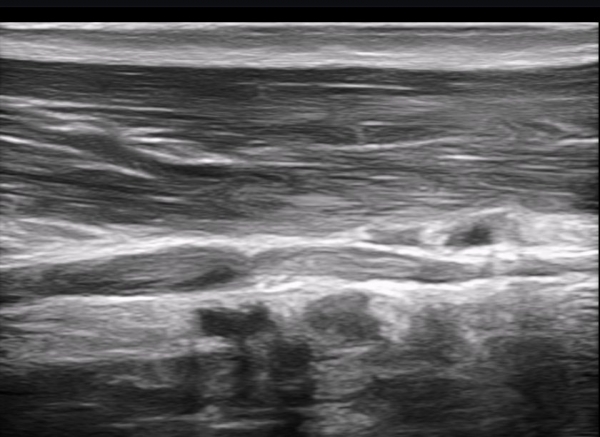

¸»´ÜÀ¸·Î À̵¿ÇÏ´Ï ±ÙÀ°ÇǺνŰæÀÌ Á¤»êÀûÀ¸·Î °üÂûµÈ´Ù(»çÁø 3).

±ÙÀ°ÇǺνŰæÀÇ Á¾´Ü¸é°Ë»ç¿¡¼­ ±ÙÀ°ÇǺνŰæÀÇ ±¹¼ÒÀû ÇùÂø°ú ±ÙÀ§ºÎÀÇ Àú¿¡ÄÚ ºÎÁ¾ÀÌ °üÂûµÈ´Ù

(»çÁø 4, 5, 6,7) À̰ÍÀº ½Å°æÀÇ ¿°Àü(torsion)¿¡ ºÎÇÕÇÏ´Â ¼Ò°ßÀÌ´Ù.